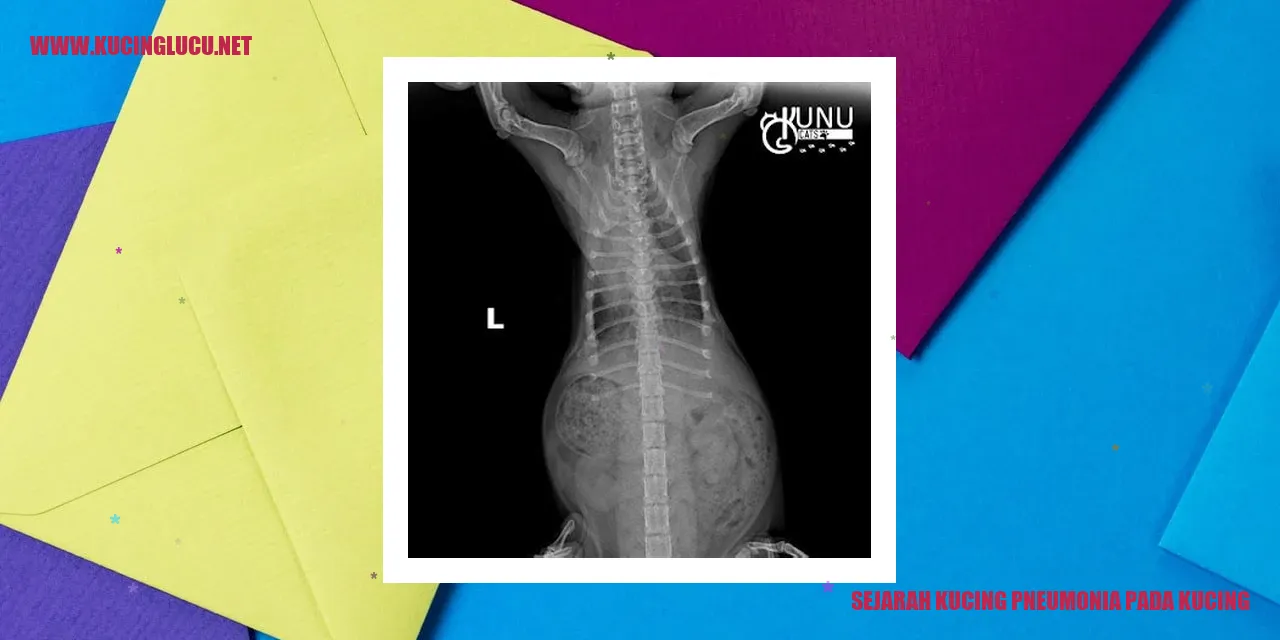

Karakteristik Fisik Kucing Terkena Pneumonia

Pneumonia pada kucing adalah kondisi gangguan saluran pernapasan yang dapat mengenai paru-paru dan sistem pernapasan mereka. Terdapat beberapa ciri fisik kucing yang dapat memberikan petunjuk penting tentang adanya pneumonia pada mereka.

Pertama, kucing yang terkena pneumonia umumnya akan mengalami batuk yang berlarut-larut. Batuk ini dapat terdengar sebagai batuk kering atau batuk dengan produksi dahak yang berlebihan. Selain itu, kucing juga bisa mengalami kesulitan bernapas dan mengeluarkan suara napas yang tidak normal, seperti mengi atau mendengus.

Perubahan pada suara napas juga bisa diamati pada kucing dengan pneumonia. Suara napas yang berat, napas yang terengah-engah, atau bernapas dengan napas yang pendek dapat menjadi tanda-tanda masalah pada sistem pernapasan. Selain itu, kucing juga mungkin menunjukkan kelelahan, lesu, dan kekurangan energi dibandingkan dengan kondisi biasanya.

Kehadiran demam juga dapat mengindikasikan bahwa kucing menderita pneumonia. Jika suhu tubuh kucing melebihi 39°C, ini dapat menjadi pertanda adanya infeksi yang sedang berlangsung. Kurangnya nafsu makan dan penurunan berat badan juga bisa terjadi akibat pneumonia yang dapat memengaruhi kondisi keseluruhan kesehatan kucing.

Sangat penting untuk memerhatikan ciri-ciri fisik ini dan segera membawa kucing ke dokter hewan jika ada kekhawatiran mengenai pneumonia. Kucing yang terkena pneumonia membutuhkan perawatan medis yang tepat guna memulihkan kesehatannya dan mencegah terjadinya komplikasi yang lebih serius.

Pneumonia pada kucing dapat didiagnosis oleh dokter hewan melalui pemeriksaan fisik, analisis darah, sinar-X, ataupun tes tambahan seperti tes dahak atau tes diagnostik lainnya. Hasil pemeriksaan ini sangat penting untuk menentukan penyebab pneumonia serta memberikan pengobatan yang tepat.